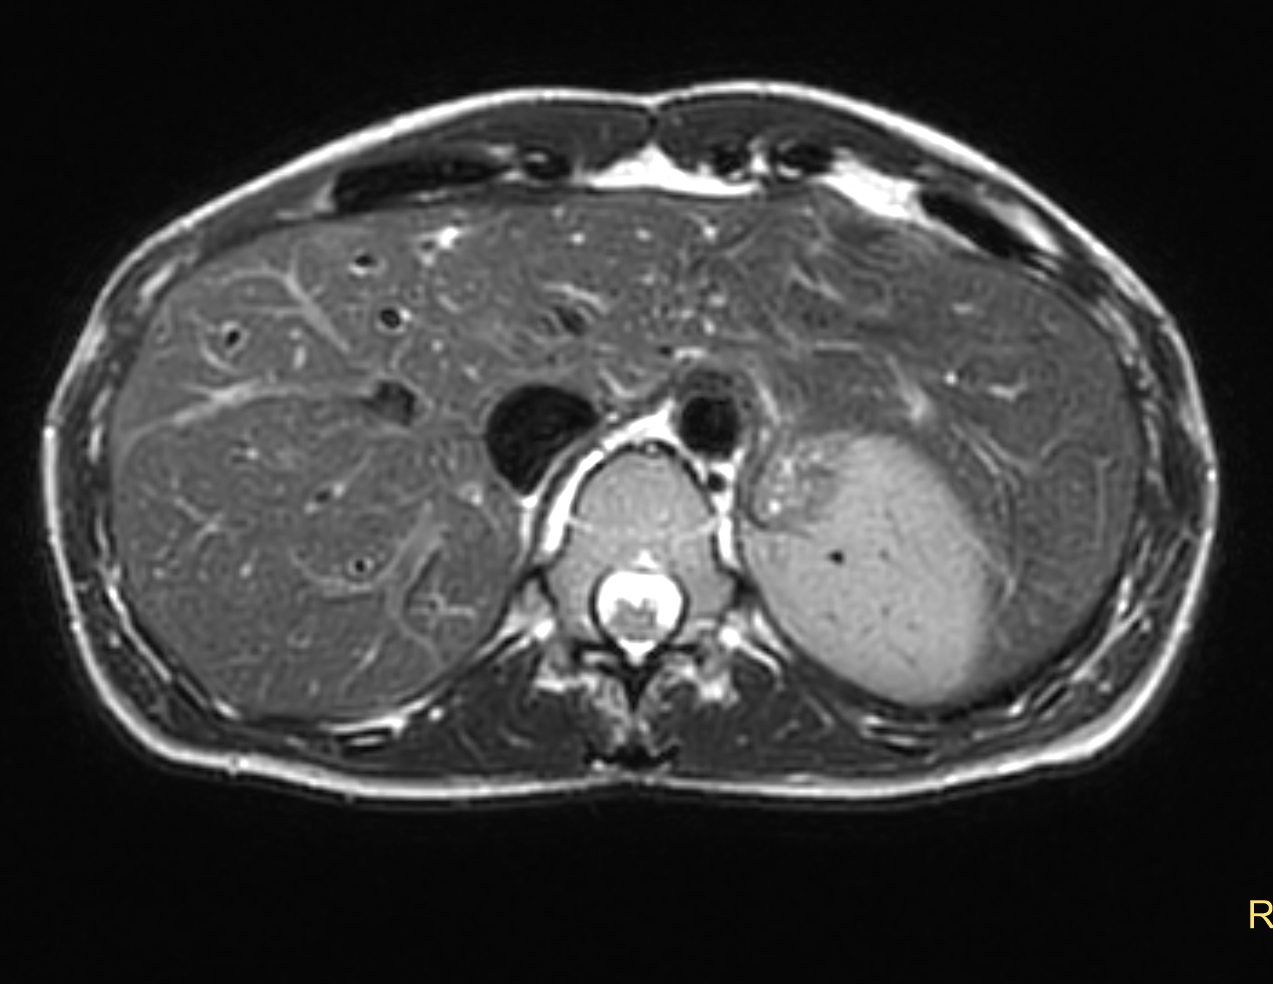

Axial mDIXON XD - T1w FFE (Water only)